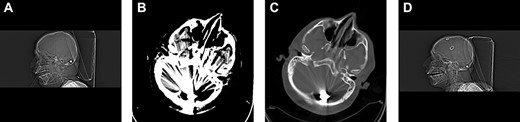

After 10 days, the patient’s neurological status worsened. Painful stimuli elicited purposeful movements of the right arm and leg. However, further examination revealed left hemiplegia with anisocoria. Emergent unenhanced head CT revealed the spontaneous migration of the bullet from the posterosuperior side of the mesencephalon to the occipital region on the left side (Fig. 2). Moreover, hydrocephalus improved. The patient’s cerebrospinal fluid was thoroughly examined for the presence of bacteria. However, the cerebrospinal fluid was sterile. Surgery was performed immediately on the ventriculoperitoneal shunt to treat hydrocephalus. On the third day after surgery, the patient could follow simple commands and showed increasingly purposeful movement on the right side. However, left hemiplegia and anisocoria did not improve. The bullet appeared removable. Therefore, we decided to remove the migrating bullet after the patient’s neurological status improved.

Follow-up CT after 10 days of admission revealed inferior and retrograde migration of the bullet to the left cerebellar peduncle. (A) Sagittal bone window. (B) Brain. (C) Axial bone window. (D) Postshunt operation control. Sagittal bone window. Ventricular catheter is observed.